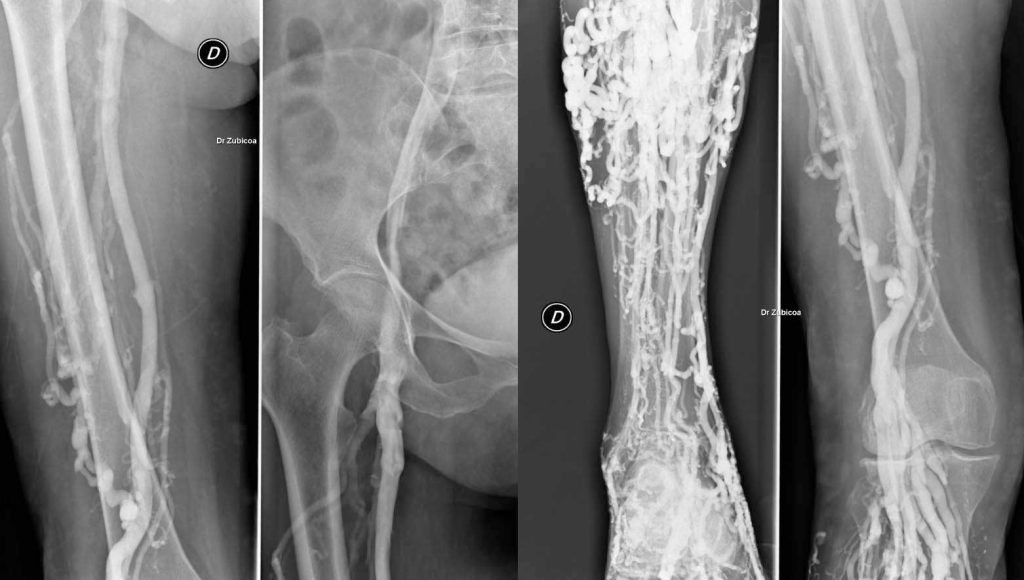

Nos especializamos en la cirugía torácica y cardiovascular, brindando soluciones avanzadas para tratar afecciones del corazón, pulmones y estructuras del tórax. Nuestro equipo de cirujanos altamente capacitados utiliza técnicas de vanguardia para ofrecer un tratamiento personalizado y seguro, asegurando la mejor atención y una recuperación óptima para cada paciente.